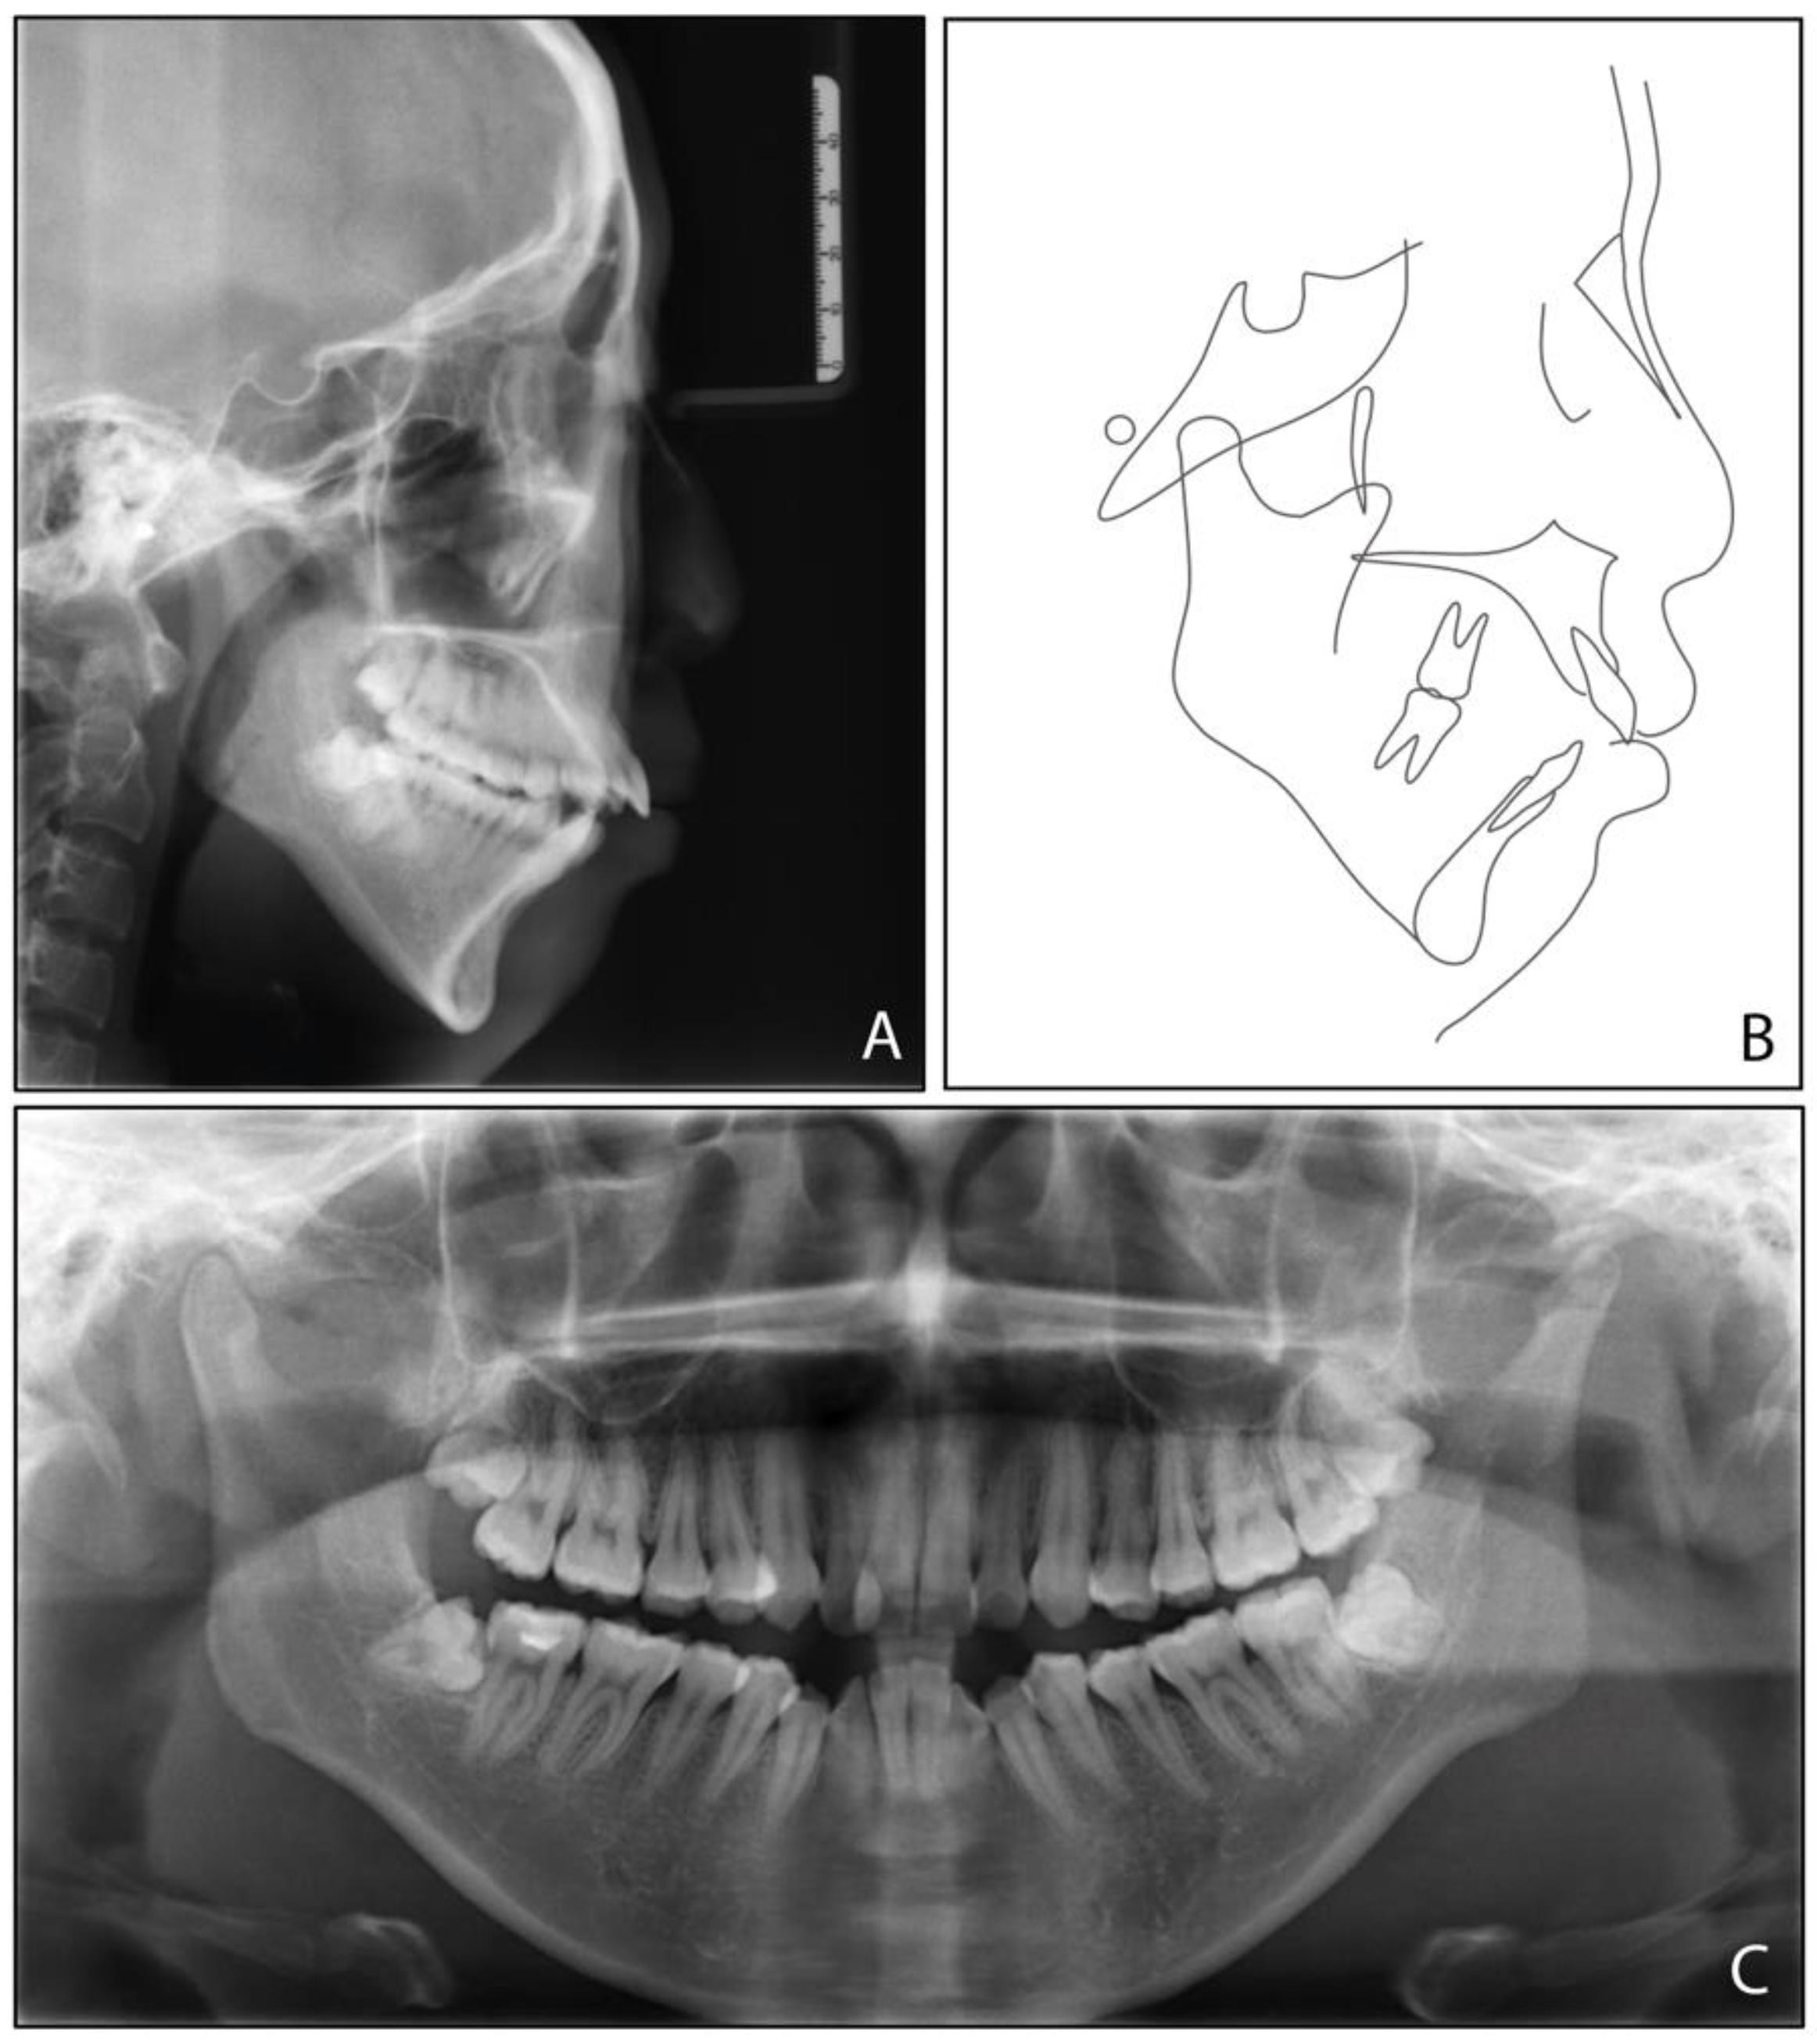

2. Case Report

2.1. Diagnosis and Etiology